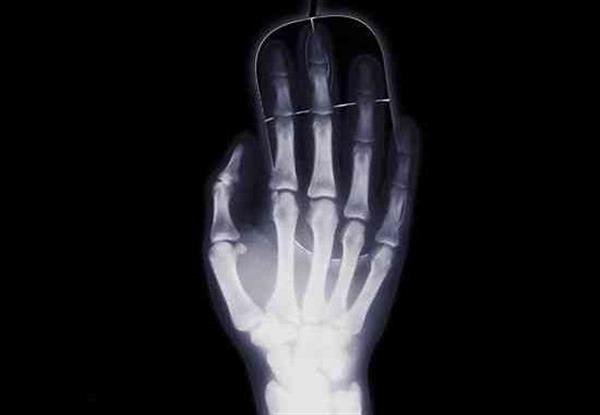

值得注意的是,這種3D打印骨頭的新方法還將使用一種叫做聚羥基丁酸酯(PHB)的可充分生物降解材料。西伯利亞聯邦大學(SFU)生物科學博士Catherine Shishatskiy解釋說,3D打印技術讓他們在設計和制作骨骼方面獲得了巨大的自由。此外,由于斷層照影技術,比如CT和核磁共振等,的使用,其3D模型的精度可以達到前所未有的水平。不可否認,掃描和3D打印技術的組合為自定義設計解剖植入物,比如3D打印骨骼,打開了大門。

參與該項目的另一位研究人員Constantine Kisterskiy還指出,通過將這種可生物兼容的材料用于骨骼的增材制造,即將該材料有效地一層層融合在一起,他們還消除了對一定化學結構和膠粘劑的需求。據e鍵打印了解,這種3D打印材料是俄羅斯Krasnoyarsk地區的科學家在以前的研究項目基礎上開發出來的。根據俄羅斯媒體的報道,SFU的一位醫學博士Ekaterina Shishatskaya曾經因為此類材料的研究在2010年獲獎。